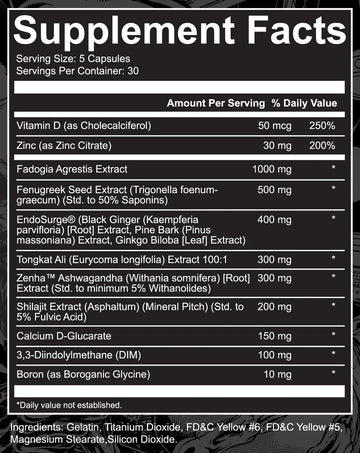

Nutrition Label